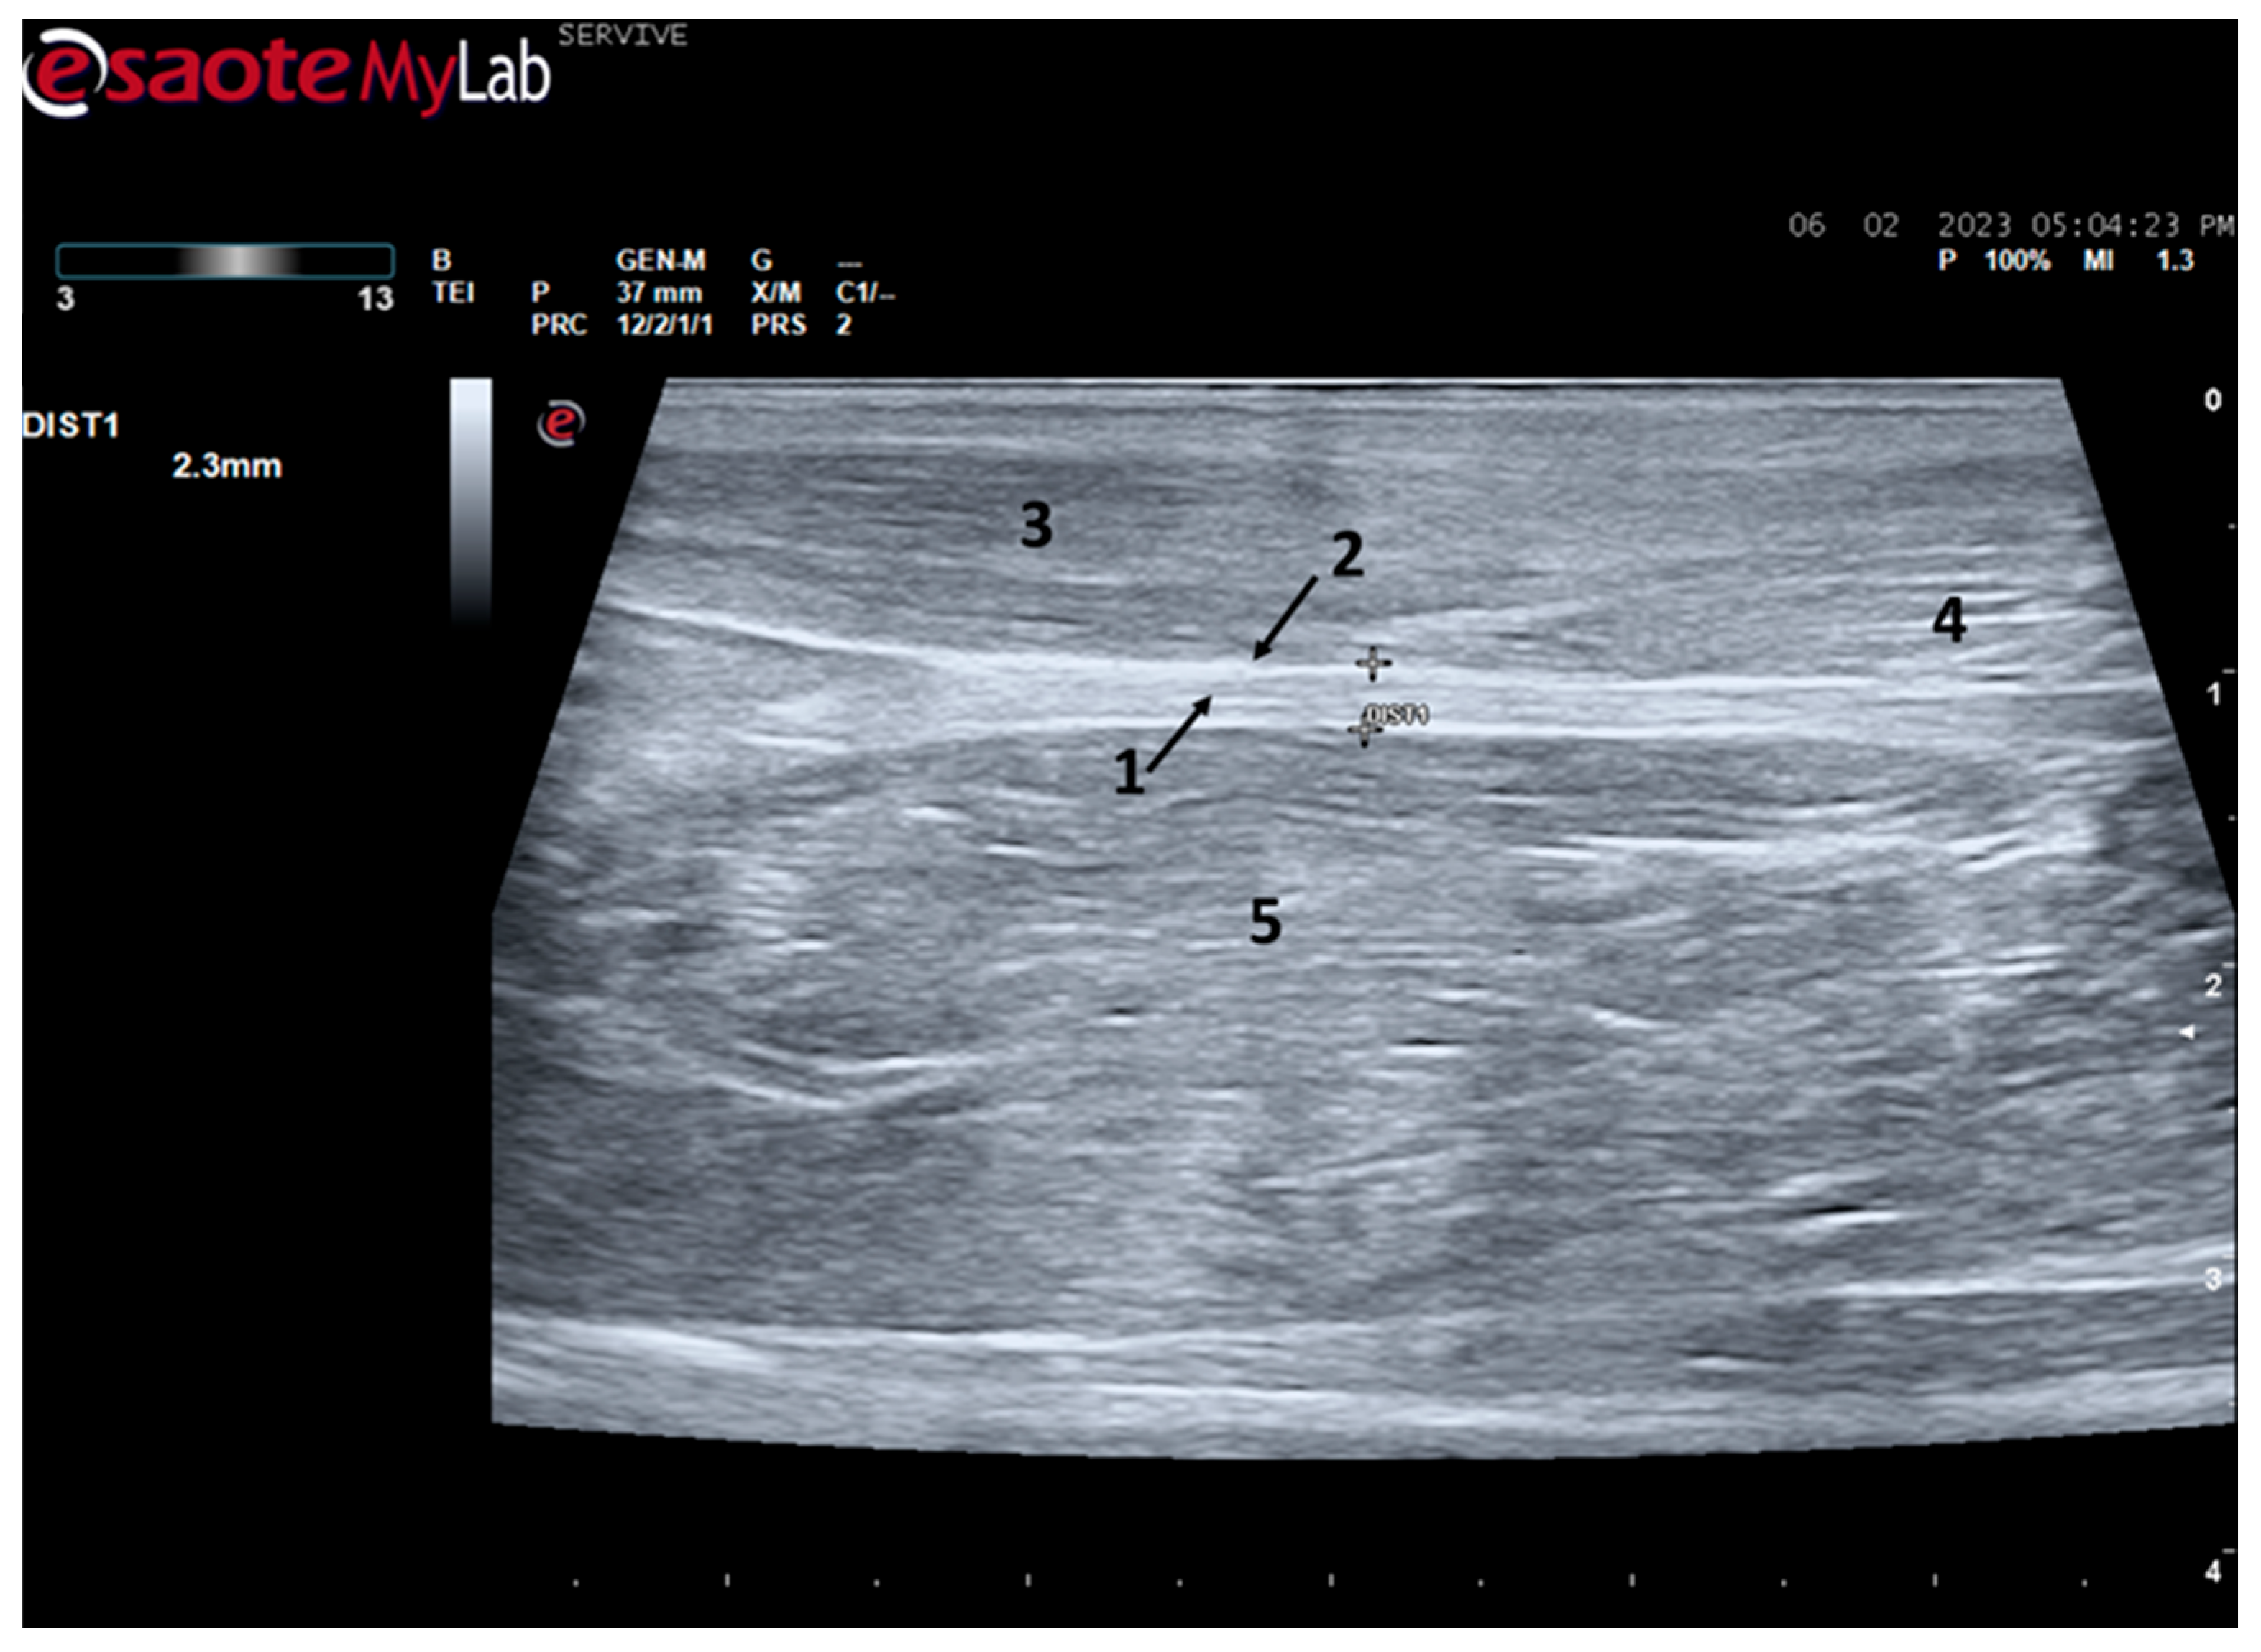

At the level of the greater ischiatic foramen, the sciatic nerve can be seen advancing between the dorsocaudal aspect of the acetabulum and cranial to the ischial tuberosity, passing over the muscle mass constituted by the gemelli and quadratus femoris muscles, close to the piriformis muscle and advancing caudally to the femur. The presence of these bony structures in the region, although they can be used as anatomical landmarks for nerve identification, can make a more proximal visualization difficult due to the curvature of the sciatic nerve and the hyperechogenicity of the bone that decreases contrast (Figure 3). Accompanying the nerve distally, it is visible between the muscles of the thigh, namely medially to the biceps femoris muscle, laterally to the adductor muscles, and caudally to the femur and the vastus lateralis muscle (Figure 4).

Figure 4.

Ultrasound image of the left sciatic nerve of a sheep nerve halfway through the thigh: (1) sciatic nerve, identified by an arrow (nerve fascicles enclosed by perineurium); (2) epineurium, identified by an arrow; (3) biceps femoris muscle; (4) piriformis muscle; (5) adductor muscles. DIST1 represents the measurement of the diameter of the sciatic nerve halfway through the thigh.

At the level of the stifle, and with great interindividual variation, the two branches of the sciatic nerve, the common peroneal nerve, and the tibial nerve, are easily observable and distinguishable, diverging from the main nerve (Figure 5). Both the sciatic nerve and its branches appear as hypoechogenic neuronal tubular structures (nerve fascicles and the perineurium) surrounded by a hyperechogenic envelope corresponding to the connective tissue nerve wrappings (epineurium) (Figure 3, Figure 4 and Figure 5). The most lateral nerve, appearing dorsally on the ultrasound image, corresponds to the common peroneal nerve and imagiologically has a slightly smaller diameter than the tibial nerve, which is more medial and appears ventrally on the ultrasound image. Accompanying both nerves distally, there is a tendency for a slight decrease in their diameter before the final ramifications, but the intended site for inducing injury to the common peroneal nerve is proximal to the point where the decrease in diameter occurs.

The sciatic nerve was easily identified mid-thigh medially to the biceps femoris muscle and caudal to the femur and vastus lateralis muscle, allowing these muscles to be used as reference points for quick identification even for less experienced ultrasonographers. Monitoring the nerve in a proximal direction makes it possible to identify its passage between the greater trochanter of the femur and the ischial tuberosity, and these bony projections can be used as a reference point for its location. More proximally is its emergence from the greater sciatic foramen. At this level, the nerve may be more difficult to identify due to its curvature and also due to its proximity to the caudal gluteal artery and vein, but the use of a color-flow Doppler may clear up any doubts. Confusion with the sacred loin trunk in this region will be more unlikely since it is at greater depth. The sciatic nerve can also be easily tracked distally to the point where it branches proximally to the stifle. As the nerve progresses, an increase in echogenicity seems to be observed, a phenomenon described in other species [16], and which is probably related to an increase in the connective tissue within the nerve. It is important to remember that this increase in the amount of connective tissue is also related to an increased likelihood of compression or stretching injuries, making it harder to observe the nerve and apply local anesthetic blocks [26]. The mean diameter of the sciatic nerve measured mid-thigh and just before its branching site is identical to that indicated in other species, such as dogs of similar size. Its ultrasound appearance is similar to that described in other species, such as humans [27], dogs [14,15], or cats [16], appearing as a hypoechogenic tubular structure covered by a hyperechogenic envelope corresponding to the epineurium, an aspect that allows its easy differentiation from soft tissues and bones in the vicinity. Before its branching site, the sciatic nerve diameter was also measured in a cross-section, rotating the probe 45 degrees from the position that allows for obtaining the longitudinal image (Figure 8). Obtaining an image in this plane proved to be more complex and made it difficult to establish anatomical relationships with neighboring structures and with the ramifications of the sciatic nerve. On the other hand, the ultrasound image reveals characteristics identical to those obtained in the regular plane, in addition to the measured diameter being the same as that obtained with the previous technique. Therefore, it was decided not to use the transverse plane for this ultrasound characterization in any of the considered nerves.